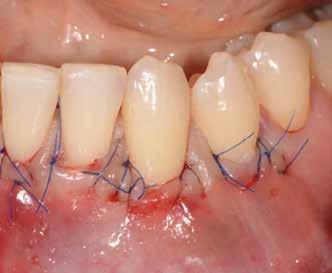

60/40 arányú keverésével történt (5–7. ábra), A-PRF és A-PRF/S-PRF membránokat készítettünk (8. ábra). Az alveólusokat a grafttal feltöltöttük, a felső front régióban vertikális augmentációt végeztünk a tervezett alveoláris csontmagasság elérésének céljából (9–10. ábra). A vertikális augmentáció támogatására titán mikrocsavarokkal rögzített, titánerősítésű teflonmembránokat alkalmaztunk, amelyekre egy rétegben A-PRF membránokat, és egy rétegben A-PRF/S-PRF membránokat helyeztünk. Az alsó állcsont esetében vertikális augmentáció nem volt szükséges, célunk az alveoláris kemény- és lágyszöveti struktúrák prezervációja volt, a graftot csak PRF memb-

ránokkal fedtük. A PRF membránok külön rögzítést egyik állcsont esetében sem kaptak (11–12. ábra). A mukogingivális lebenyt – annak megnyújtása nélkül – a helyére fektettük és varratokkal rögzítettük, per primam sebzárást nem végeztünk. A varratokat 2 hét után távolítottuk el, a varratszedésig a sebgyógyulás támogatására per os 1000 mg/nap C- és 12 000 NE/nap D-vitamint adtunk (28).

35 Ncm primer stabilitást mértünk. Nyílt gyógyulási protokollt alkalmazva az ínyformázókat is behelyeztük, amelyek körül az ínyt csomós öltésekkel zártuk (18–20. ábra) Amennyiben lehetséges, mindig nyílt gyógyulási protokollt választunk, így biztosítva elegendő időt a lágyrészek maturációjához (29). Kiemelendő, hogy az irodalmi adatoknak (30, 31, 32) és saját tapasztalatunknak megfelelően az íny biotípusának jelentős, pozitív irányú változását észleltük. Az implantátumokra 180 nap gyógyulási időszakot követően (minden implantátum stabilitása Periotesttel –8-as értékű volt) hagyományos lenyomatvételi módszer és egyéni értékű artikulátor használatával a fogtechnikus (D1 Dental Kft., Garamvári Csaba) overdenture típusú fogpótlást készített (21. ábra)